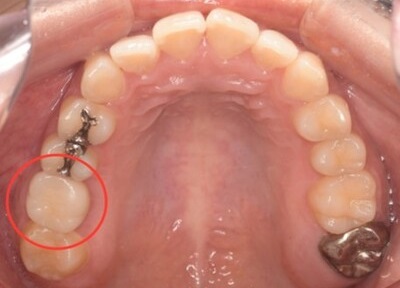

初診時口腔内写真

初診時パノラマX線写真と口腔内写真。

右上6に腫脹と排膿がみられた。

抜歯予定の歯と移植予定の歯

右上6(青丸)を抜歯し、右下8(赤丸)を移植することを計画した。

右上の抜歯後の治癒を待つため、抜歯の1ヶ月後に移植を行うこととした。